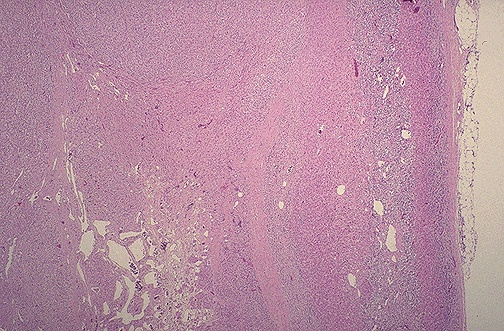

Image 7.2

At low power, the tumor is seen adjacent to compressed normal adrenal gland.